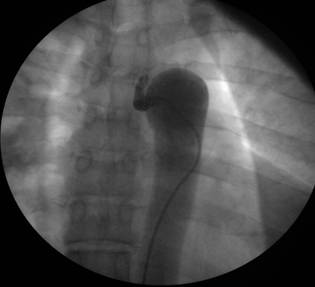

A 52-year-old obese white man was referred to our hospital because of increasing fatigue and exertional dyspnea. He had been well until 5 months previously. The patient had a medical history of dyslipidemia and hypertension. His hypertension was poorly controlled despite a combination of antihypertensive agents (beta-blocker and angiotensin receptor blocker). Physical examination showed blood pressure 140/90 in both arms, a heart rate of 74 beats/minute and an apical gallop sound (S4). Femoral pulses were palpable bilaterally but weak and delayed compared to the brachial pulses. His echocardiogram showed bicuspid aortic valve with minimal regurgitation, segmental wall motion abnormalities and mild mitral insufficiency. A cardiac silhouette at the upper limits of normal and notching of the ribs were observed on the chest radiography. Due to the significance of the cardiac dysfunction and his clinical presentation, the patient underwent a cardiac catheterization to evaluate his coronary artery disease. The left ventricular ejection fraction was significantly reduced (Ejection fraction: 30-35%). There was no evidence of mitral valve prolapse. Aortography showed a mildly dilated aortic root, minimal aortic valve insufficiency and a significant ring-like stenosis in the thoracic descending aorta (Figures 1 and 2). The gradient through this stenosis measured 80 mmHg. The coronary angiography was negative for significant focal coronary artery obstruction. The patient was then referred to cardiothoracic surgery. The procedure was done via left posterolateral thoracotomy from the fifth intercostal space. Since, the collaterals were well recognized before surgery, the procedure was achieved without major bleeding and any adverse event. Furthermore, the patient was adult and any minor bleeding has not resulted in requirement of blood transfusion. The coarctated segment was resected totally and end to end anastomosis of thoracic aorta was performed in a standart fashion. The coarctated segment was short in our patient and it was not difficult to get the two ends together without tension on the anastomosis so that we do not considered an interposition graft. The cross clamp time was 23 minutes and because the collaterals were left intact, any malperfusion syndrome has not occurred. Total hospital stay after procedure was only four days. After the 1-year follow-up visit, the patient was in good clinical condition.

Figure 2

Descending aortography